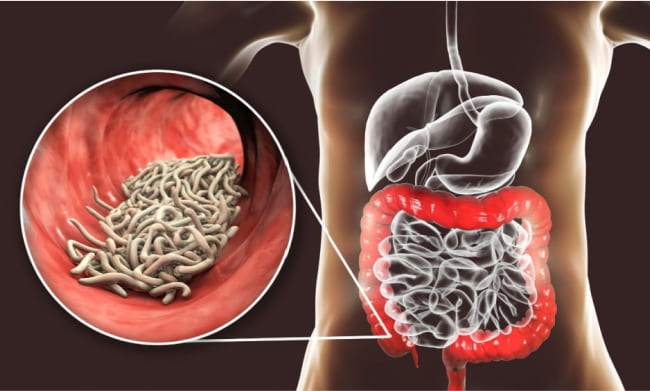

After months of costly medical tests, the diagnosis was finally revealed: a parasitic infection. Astonishingly, about 67% of Juan's body was infested with parasites. They were everywhere! I was stunned and puzzled about their origin. Our home is always immaculate, cleaned two to three times a week. I'm meticulous about buying quality products and thoroughly cleaning them. It was hard to believe that all these symptoms were due to a parasitic infection!

The statistic that 850,000 people in the Philippines die annually without knowing that parasites are the cause of their death is both alarming and a critical public health concern. Parasites are indeed "invisible killers," lurking in everyday items like fish, meat, water, and even fruits and vegetables purchased from supermarkets or markets.

This highlights the importance of food safety, proper hygiene, and awareness about parasitic infections. It underscores the need for better public education on the risks of parasitic infections, how they can be contracted, and the symptoms to watch out for. Additionally, it stresses the importance of access to healthcare and diagnostic facilities that can detect and treat such infections effectively.

In regions where such infections are prevalent, routine screening and preventive measures could significantly reduce the incidence and impact of parasitic infections. Awareness campaigns, improved sanitation, and access to clean water are also critical components of controlling and preventing the spread of parasites.